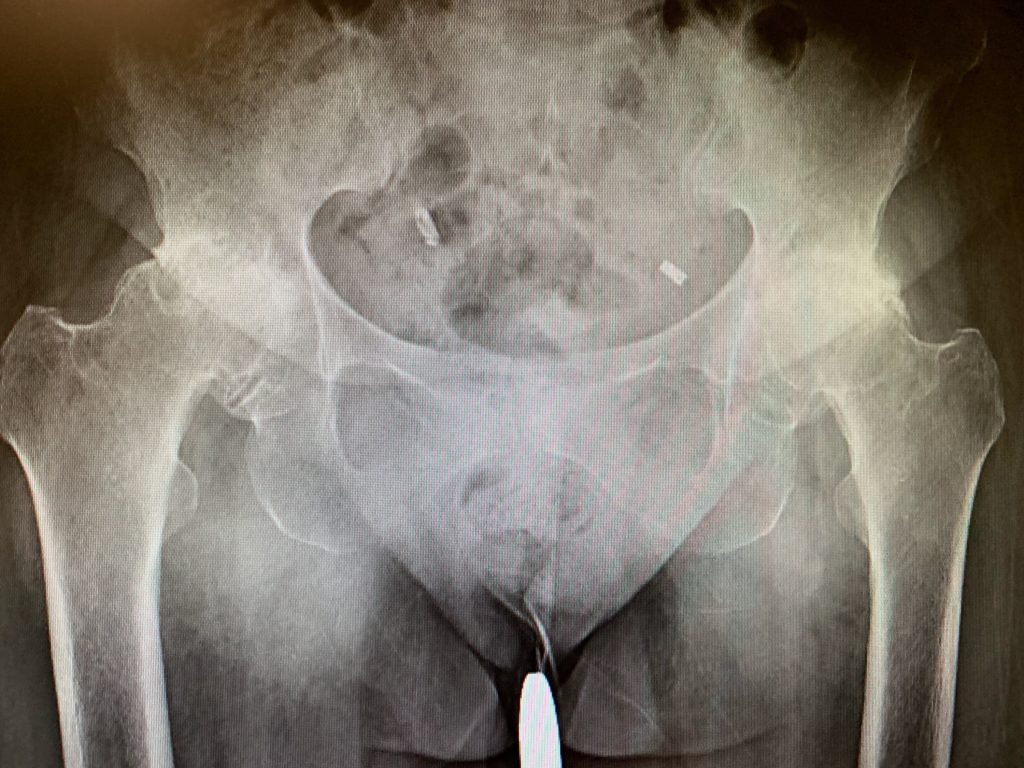

Bilateral hip replacement surgery. What is a staged bilateral total hip replacement? But sometimes, hip replacements are done on both sides of the hip (bilateral). Hip replacement surgery involves removing parts of the hip joint and replacing them with synthetic parts.

Bilateral hip replacement occurs when hip replacement surgery is done on both hips at the same time. Almost 2 weeks after bilateral hip replacement surgery. I have very little dialogue with kaiser so i was wondering if there are any bilateral hippies out.

A “simultaneous bilateral joint replacement” refers to a double replacement where both hips or knees are replaced in the same surgical setting. Read on as we talk through the pros and. Double hip replacement (or simultaneous bilateral total hip replacement) in which both hip joints are replaced in one surgery.

Having both sides replaced on the same day is called “bilateral” replacement surgery. This is called bilateral total hip replacement. Surgeries are planned to be performed several monthsapart one from the other, requiring two hospital stays, two episodes of anesthesia and two rehabilitation periods.